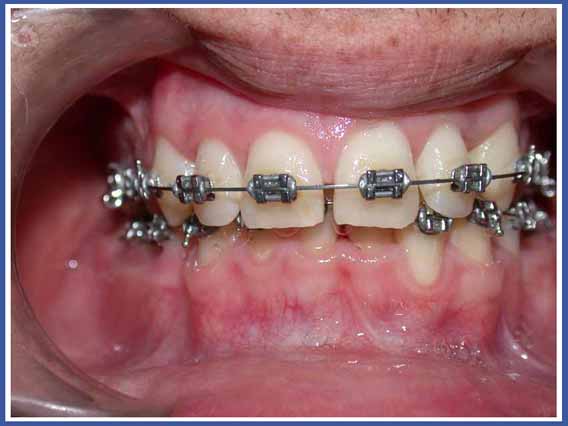

סמכים אורתודונטים (גשר) Brackets:

האמצעי הנפוץ ביותר כיום להזזת שיניים. הסמכים המודבקים לשיניים והחוט שעובר ביניהם מאפשרים להזיז את השיניים בכל שלושת המימדים בשליטה מלאה על התנועה, בניגוד לפלטות שיכולות להזיז שיניים רק בהטיה (רק לשנות את הזווית של השן בלסת). סמכים יכולים להיות מתכתיים או שקופים.

לסמכים המודבקים לשיניים יש יתרונות רבים אך יש להם גם חסרונות. החסרון העיקרי הוא הצטברות שאריות מזון וחיידקים עליהם. כדי למנוע סכנה לעששת (חורים) מסביב לסמכים, יש להקפיד על צחצוח שיניים קפדני במהלך הטיפול, ולהמנע ככל האפשר ממזון המזרז את התפתחות העששת (מזון עשיר בסוכר).

הנחיות לשמירה על הגיינה בזמן הטיפול האורתודונטי באמצעות סמכים (גשר):

חשוב מאד לנקות בין השיניים והטבעות, שכן לחיידקים יש נטייה גדולה יותר להימצא במקומות אליהם קשה לנו להגיע. פעולה זו תמנע בעיות ועששת גם לאחר סיום הטיפול והורדת הסמכים.